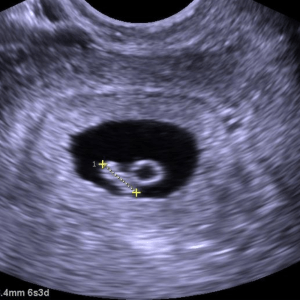

Actualmente trabajo como profesionista independiente. Realizo estudios de ultrasonido de todo tipo: abdominal, renal, hepatobiliar, ginecológico, prostático, tiroideo, inguinal, escrotal, así como estudios de arterias y venas (Doopler color y espectral) en brazos, piernas y cualquier otro órgano del cuerpo. En caso de indicación médica puedo realizar biopsias del cuello (tiroides y ganglios), abdomen (hígado, riñón) o próstata, así como extraer líquido acumulado en la pleura (membrana que recubre los pulmones) y en el abdomen, entre otros.